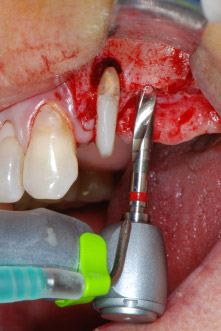

En primer lugar, en un intento por gestionar el problema endo-periodontal, el resto de la superficie radicular se desbridó con cuidado con un equipo piezoeléctrico (Piezomed de W&H, utilizado con el inserto S1 con forma de espátula, concebido en un principio para la erosión de la pared lateral del seno) (figura 4). A continuación, el ápice se erosionó con el mismo instrumento para eliminar el tejido apical infectado residual y reducir las posibles ramificaciones accesorias del canal radicular (apicectomía) (figura 5). No fue necesario realizar un retrorellleno, puesto que la obturación ortógrada se acababa de revisar.

Antes de colocar el implante, el tejido infectado del hueso alveolar ubicado en el lugar del implante y alrededor de los dientes del pilar se retiró con un inserto concebido en un principio para modelar huesos y recoger virutas óseas: Piezomed y el inserto B5 (figuras 6 y 7).

En el siguiente paso, los lechos del implante se prepararon en las posiciones 25 y 26 con instrumentos rotatorios, utilizando un contra-ángulo con un coeficiente de transmisión de 20:1 (WS-75 L, W&H), junto con el nuevo potente motor de implantes Implantmed de W&H (figuras 8 y 19).